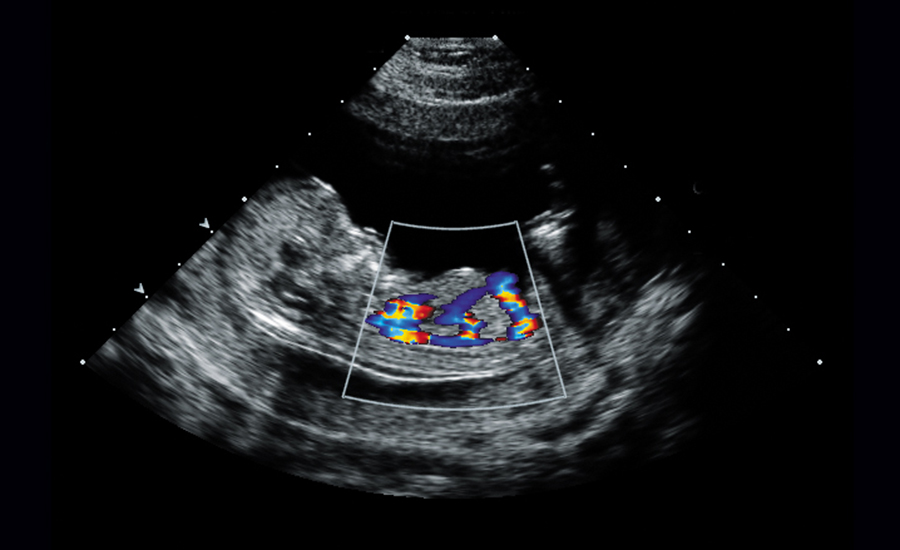

अल्ट्रासाउण्ड जस्तै प्रविधिबाट गर्भवती महिलाको पेटभित्रको बच्चाको मुटु परीक्षण गर्ने प्रविधिलाई फिटल इकोकार्डियोग्राफी भनिन्छ । यसले गर्भवती महिलाको गर्भमा हुर्किरहेको भ्रुणको मुटुलाई प्रष्ट देखाउँछ । मुटु स्वास्थ्य, यसको विकासको परीक्षण गर्ने यो प्रविधिले भ्रुणको मुटुको संरचना र कार्यक्षमतालाई विस्तृत रुपमा अवलोकन गर्न मद्दत गर्छ । मुटुमा कुनै प्रकारका चालसम्बन्धी गडबडीलाई पनि पहिचान गर्न यस प्रविधिले मद्दत गर्न सक्छ । गर्भभित्रको बच्चाको मुटुको समस्यालाई समयमै पहिचान गर्न, उचित उपचारमा सहयोग पुर्याउनुका साथै पछि आउन सक्ने जोखिमको पूर्वतयारी गर्न पनि सहयोग पुर्याउँछ ।

सामान्यतया फिटल इकोकार्डियोग्राफी गर्भावस्थाको १८ देखि २० हप्ताको बीचमा गरिन्छ । स्वप्रतिरक्षा रोग हुने गर्भवतीको शिशुमा मुटुको चालको गडबडी हुने जोखिम हुन्छ । यसलाई समयमै पत्ता लगाई उपचार गर्दा यसको नतिजा राम्रो हुने हुँदा त्यस्ता महिलाले १६ हप्तादेखि नै फिटल इकोकार्डियोग्राफी गराउन सकिन्छ ।

भ्रूण इकोकार्डियोग्राफी सामान्य स्क्यान जस्तै गरी गरिन्छ, जसमा गर्भवती महिलालाई खाना खाएर आउन सल्लाह दिइन्छ । यो प्रक्रिया गर्दा ४० देखि ४५ मिनेट लाग्छ । गर्भमा रहेको बच्चाको अवस्थाअनुसार यसले कम वा बढी समय लिन सक्छ । भ्रूण इकोकार्डियोग्राफी अनुभवी चिकित्सकबाट मात्र गराइन्छ ।